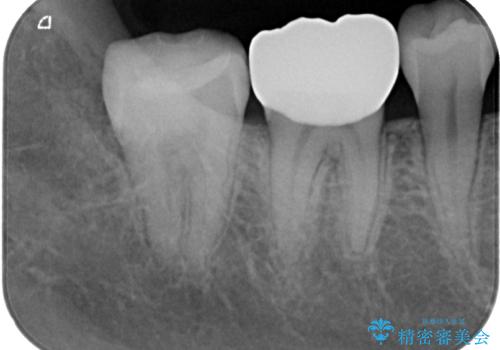

- 当院で矯正後に銀歯が目立つのでやり替えたいと来院された患者様です。銀色の詰め物(メタルインレー)と歯の間に隙間を認め、あまり歯を削りたくないとのことで患者様と相談の結果右下の7番目の歯はセラミックインレー、右下の6番目の歯はメタルインレーが大きいためフルジルコニアクラウンでの治療を行うことになりました。

拡大鏡視野下で、銀色の詰め物(メタルインレー)、保険のプラスチック、虫歯の除去を行い、セラミックインレー、フルジルコニアクラウンに適した形に整えました。

特に異常もなく見た目、噛み合わせともに満足していただけました。

ラバーダム防湿を行い、セラミックの接着をすることで、唾液や血液などの接着阻害因子を排除することができます。